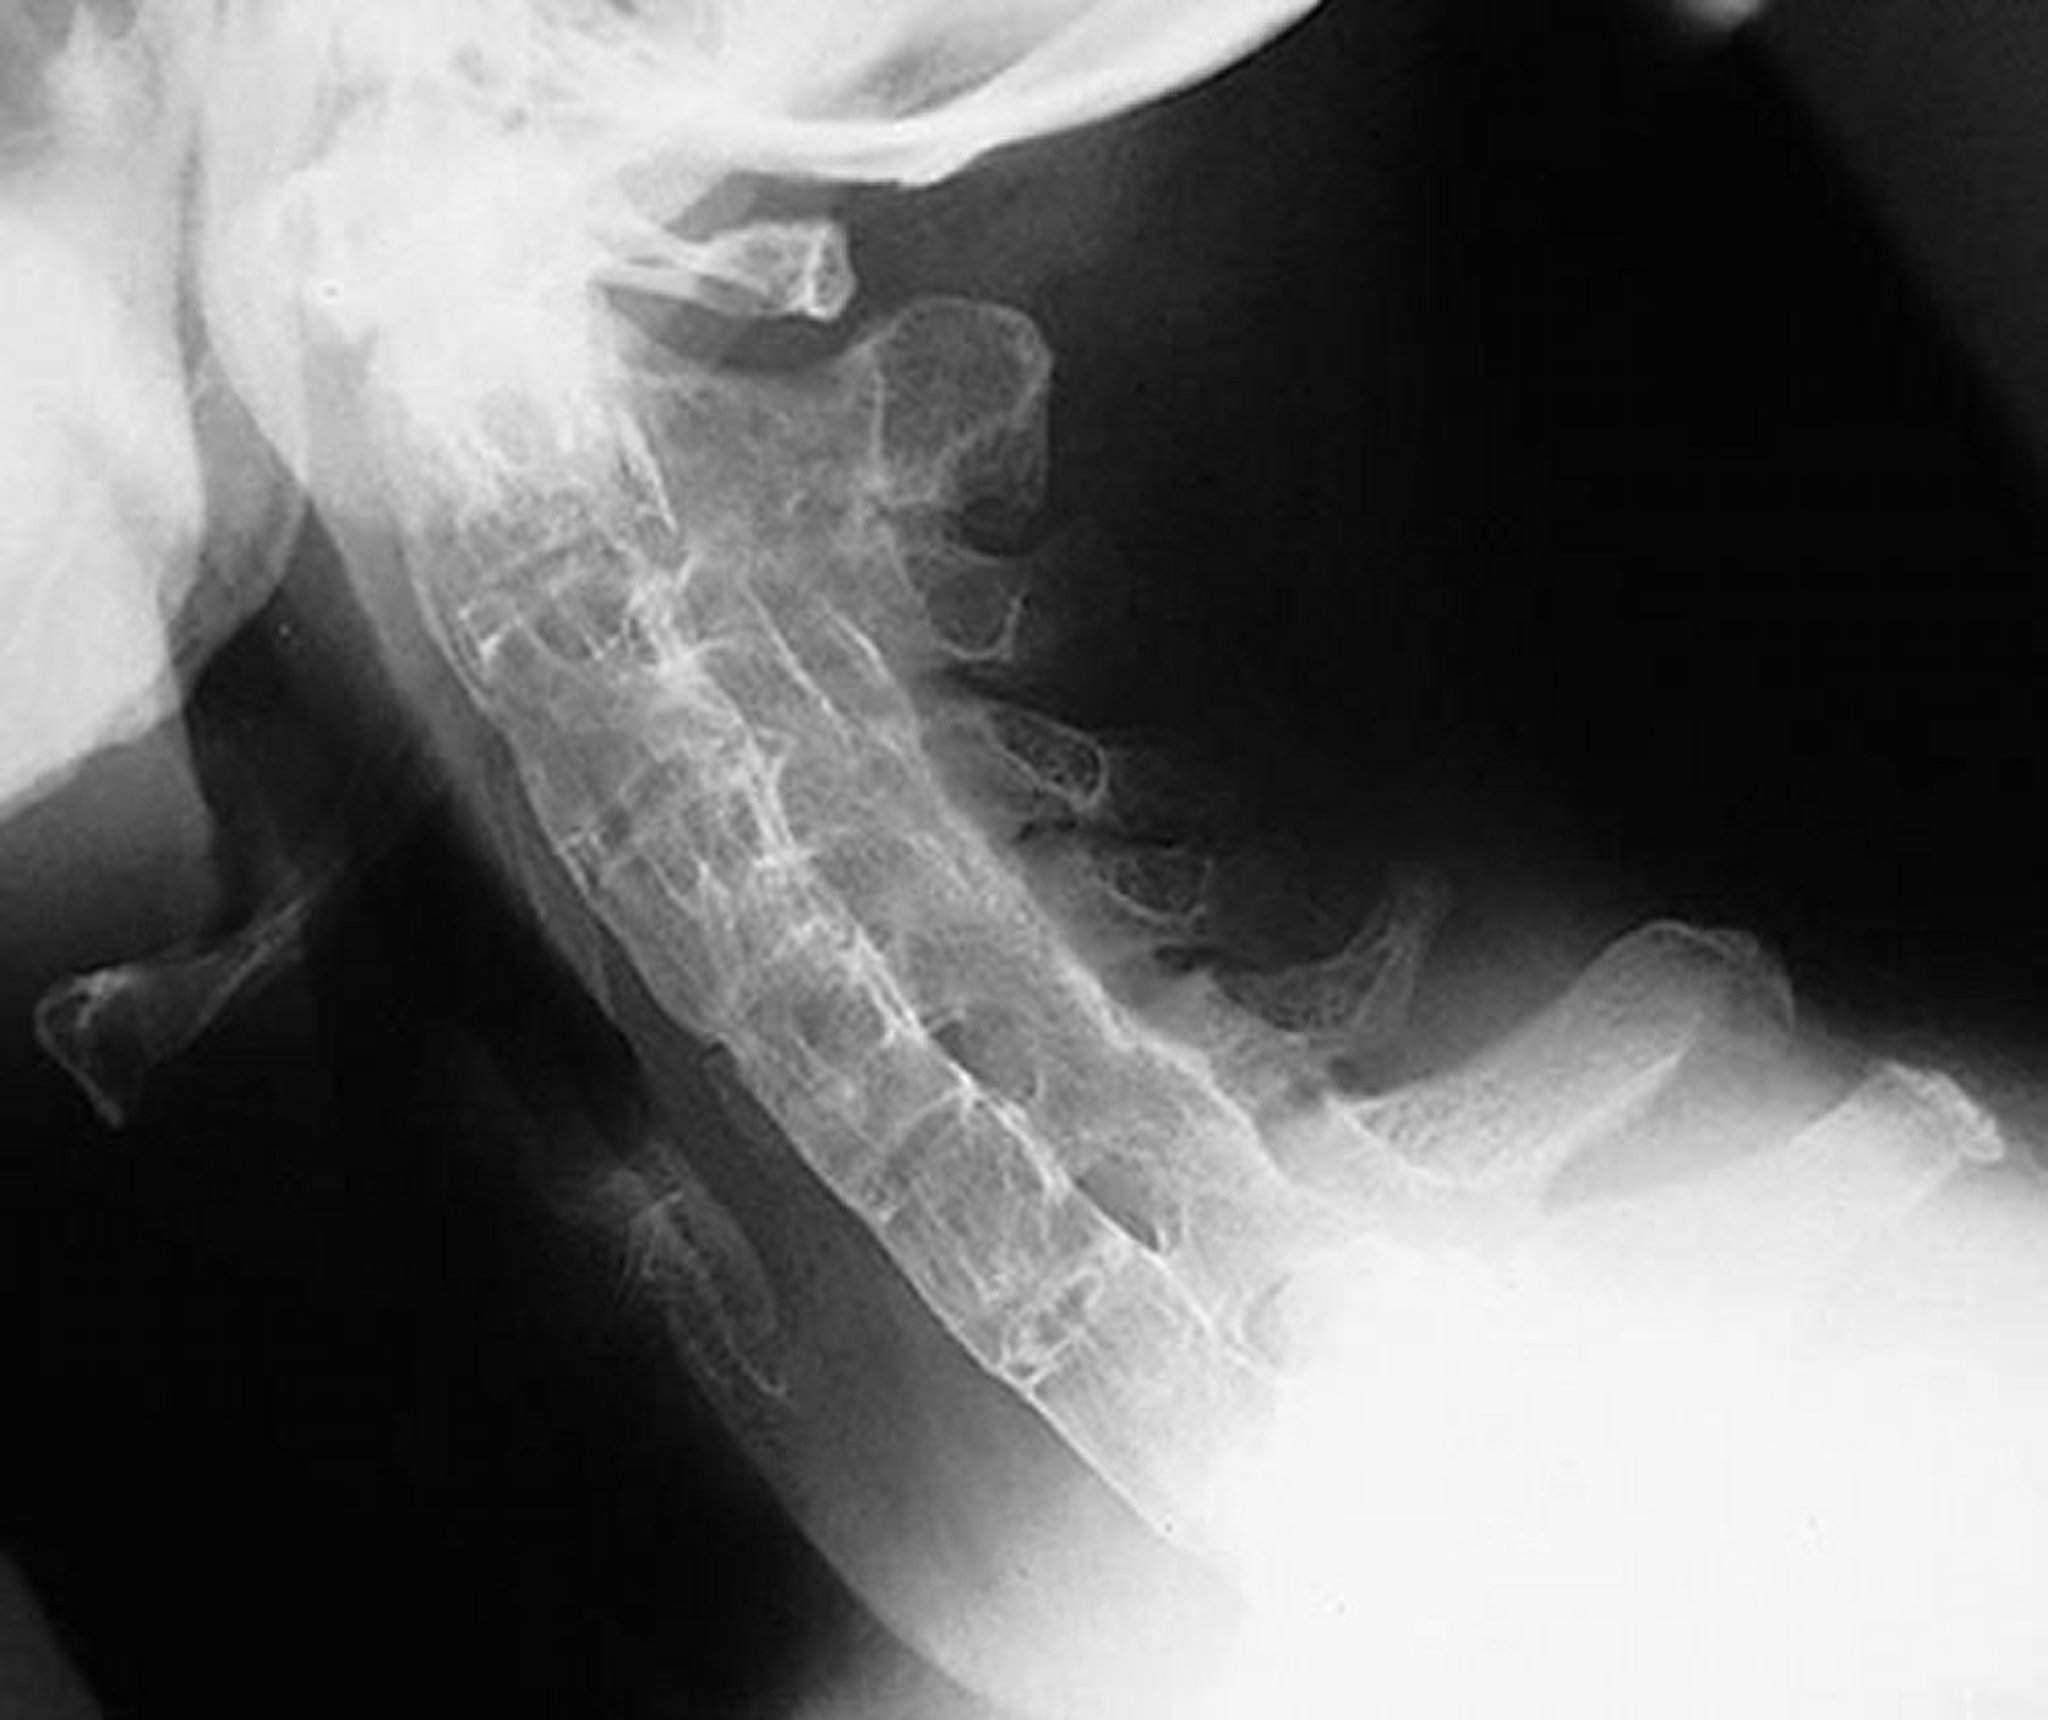

Columna de bambú en la espondilitis anquilosante

Vista lateral de la columna cervical de un paciente con espondilitis anquilosante grave y de larga evolución que muestra rigidez en la columna cervical. La columna está completamente anquilosada (“columna de bambú”) debido a la presencia de sindesmofitos, la fusión de las articulaciones cigapofisarias y la calcificación del ligamento paraespinal.

By permission of the publisher. From Asim Khan M: Atlas of Rheumatology. Edited by G Hunder. Philadelphia, Current Medicine, 2005.